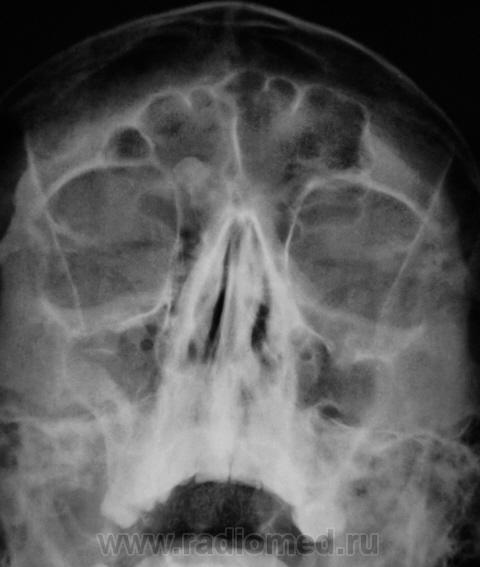

Касательно пристеночного уплотнения справа в в/ч пазухе- вполне возможно суммационное искажение из-за неправильной укладки,с учетом клиники-я бы перестраховался и назначил томограмму(в идеале-малодозовый режим СКТ на ППН). Можно назначить контроль в динамике.

что-то плотное в правой лобной пазухе- остеома?

Образование правой лобной пазухи,пристеночное утолщение слизистой пр.гайморовой пазухи. Как всегда может помочь томограмма.

Остеома с типичной локализацией. Неосложненная.

Снимок хорошего качества, в стандартной укладке, а то, что голова несколько наклонена, так это, не суть важно - пациент виноват.

Наклон головы и есть неправильная укладка,если я не ошибаюсь,хотя идеального ничего и никого нет, а по качеству изображения- "5" баллов,тут не поспоришь!!!